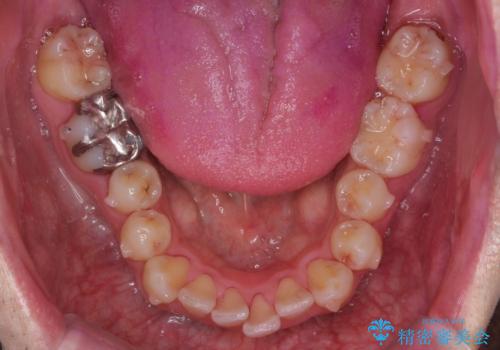

出っ歯と歯のねじれ 非抜歯で 30代男性

右の歯並びが1本分上が前にずれていました。

奥歯のかみ合わせを特に変えず、前歯の並びを整える治療をおこないました。

奥歯のかみ合わせは1本分ずれているとはいえ、1歯対2歯の交互のかみ合わせになっているため、そのままにしてもそこまで大きなデメリットはありません。

今回は右のかみ合わせはそのままにしました。左は特に初めから問題ない状態でした。

右のかみ合わせを変えず部分矯正にしたことによって、治療が短期間で済み、また、ワイヤーでなくインビザラインで治療が可能、歯も抜かなくて済むなどメリットの多い方法であるといえます。